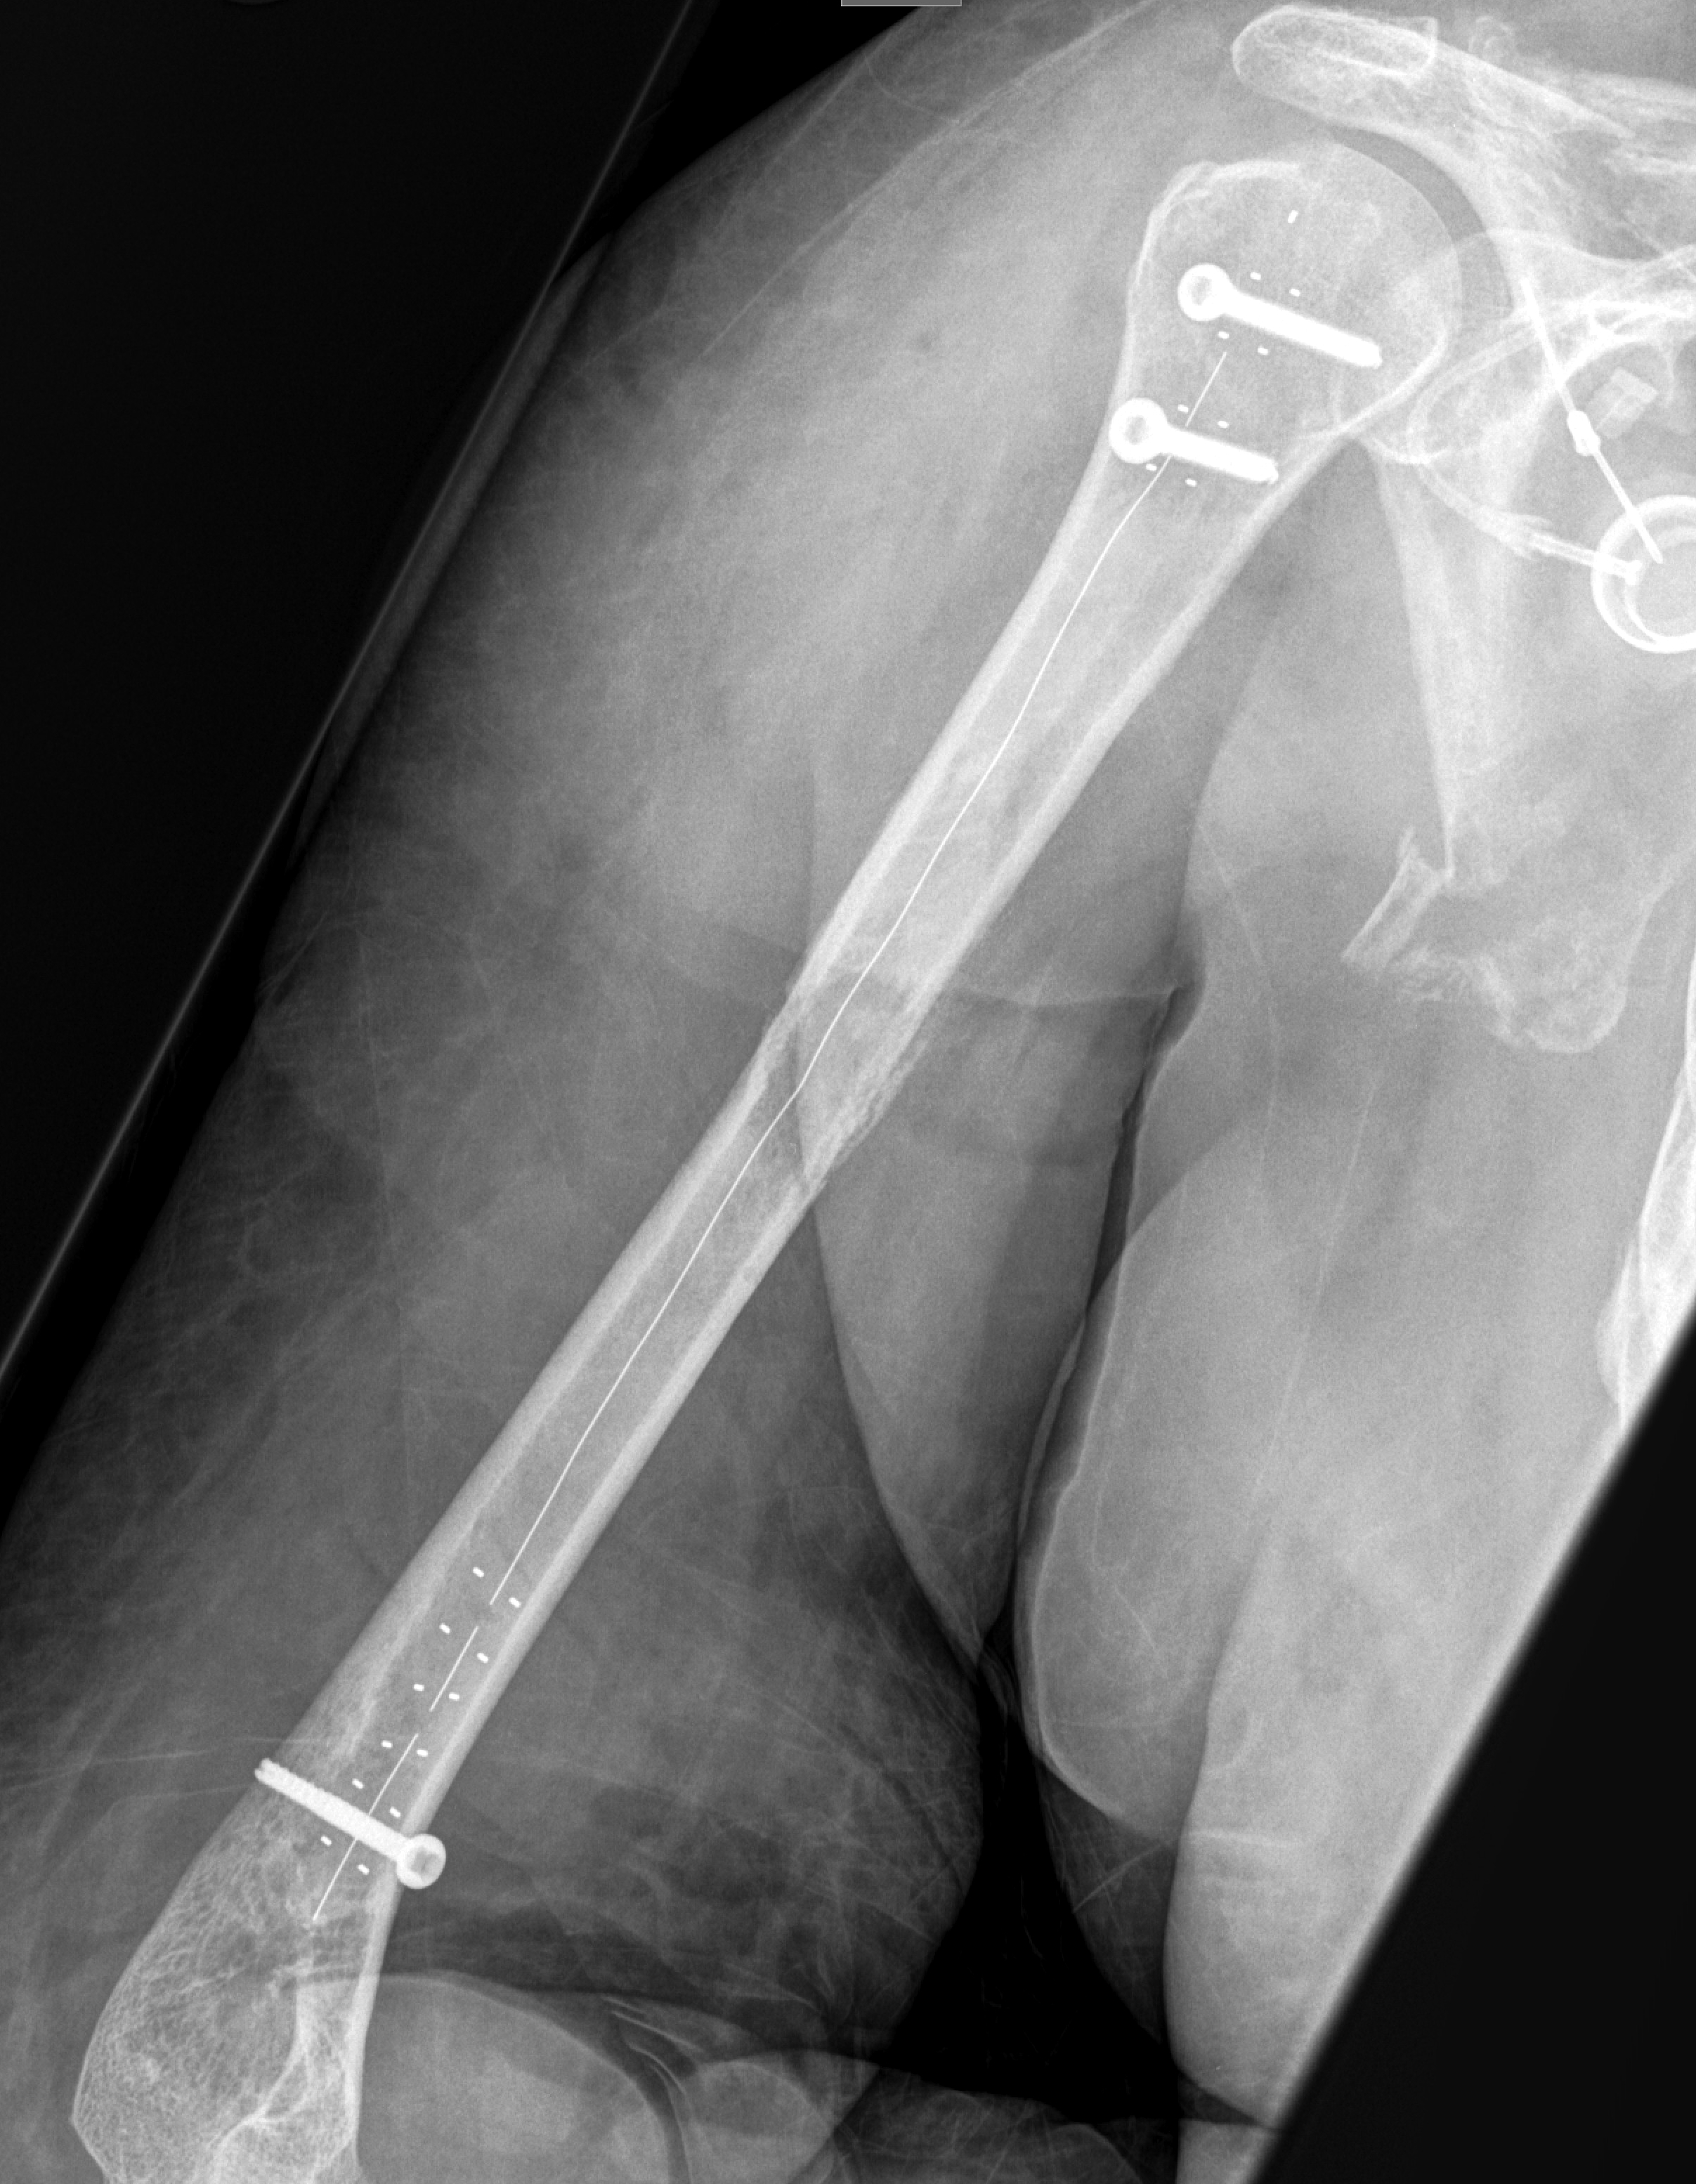

Интрамедуллярный стержень

Интрамедуллярный стержень 115 фотографий